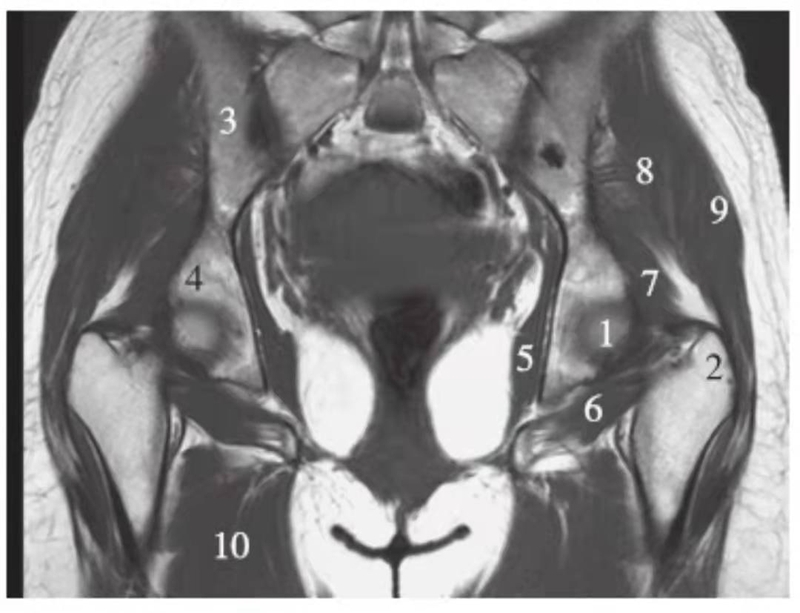

正常髋关节经股骨头后缘层面T1WI像

1.股骨头;2.大转子;3.髂骨;4.坐骨;5.闭孔内肌;6.闭孔外肌;7.臀小肌;8.臀中肌;9.臀大肌;10.内收肌群